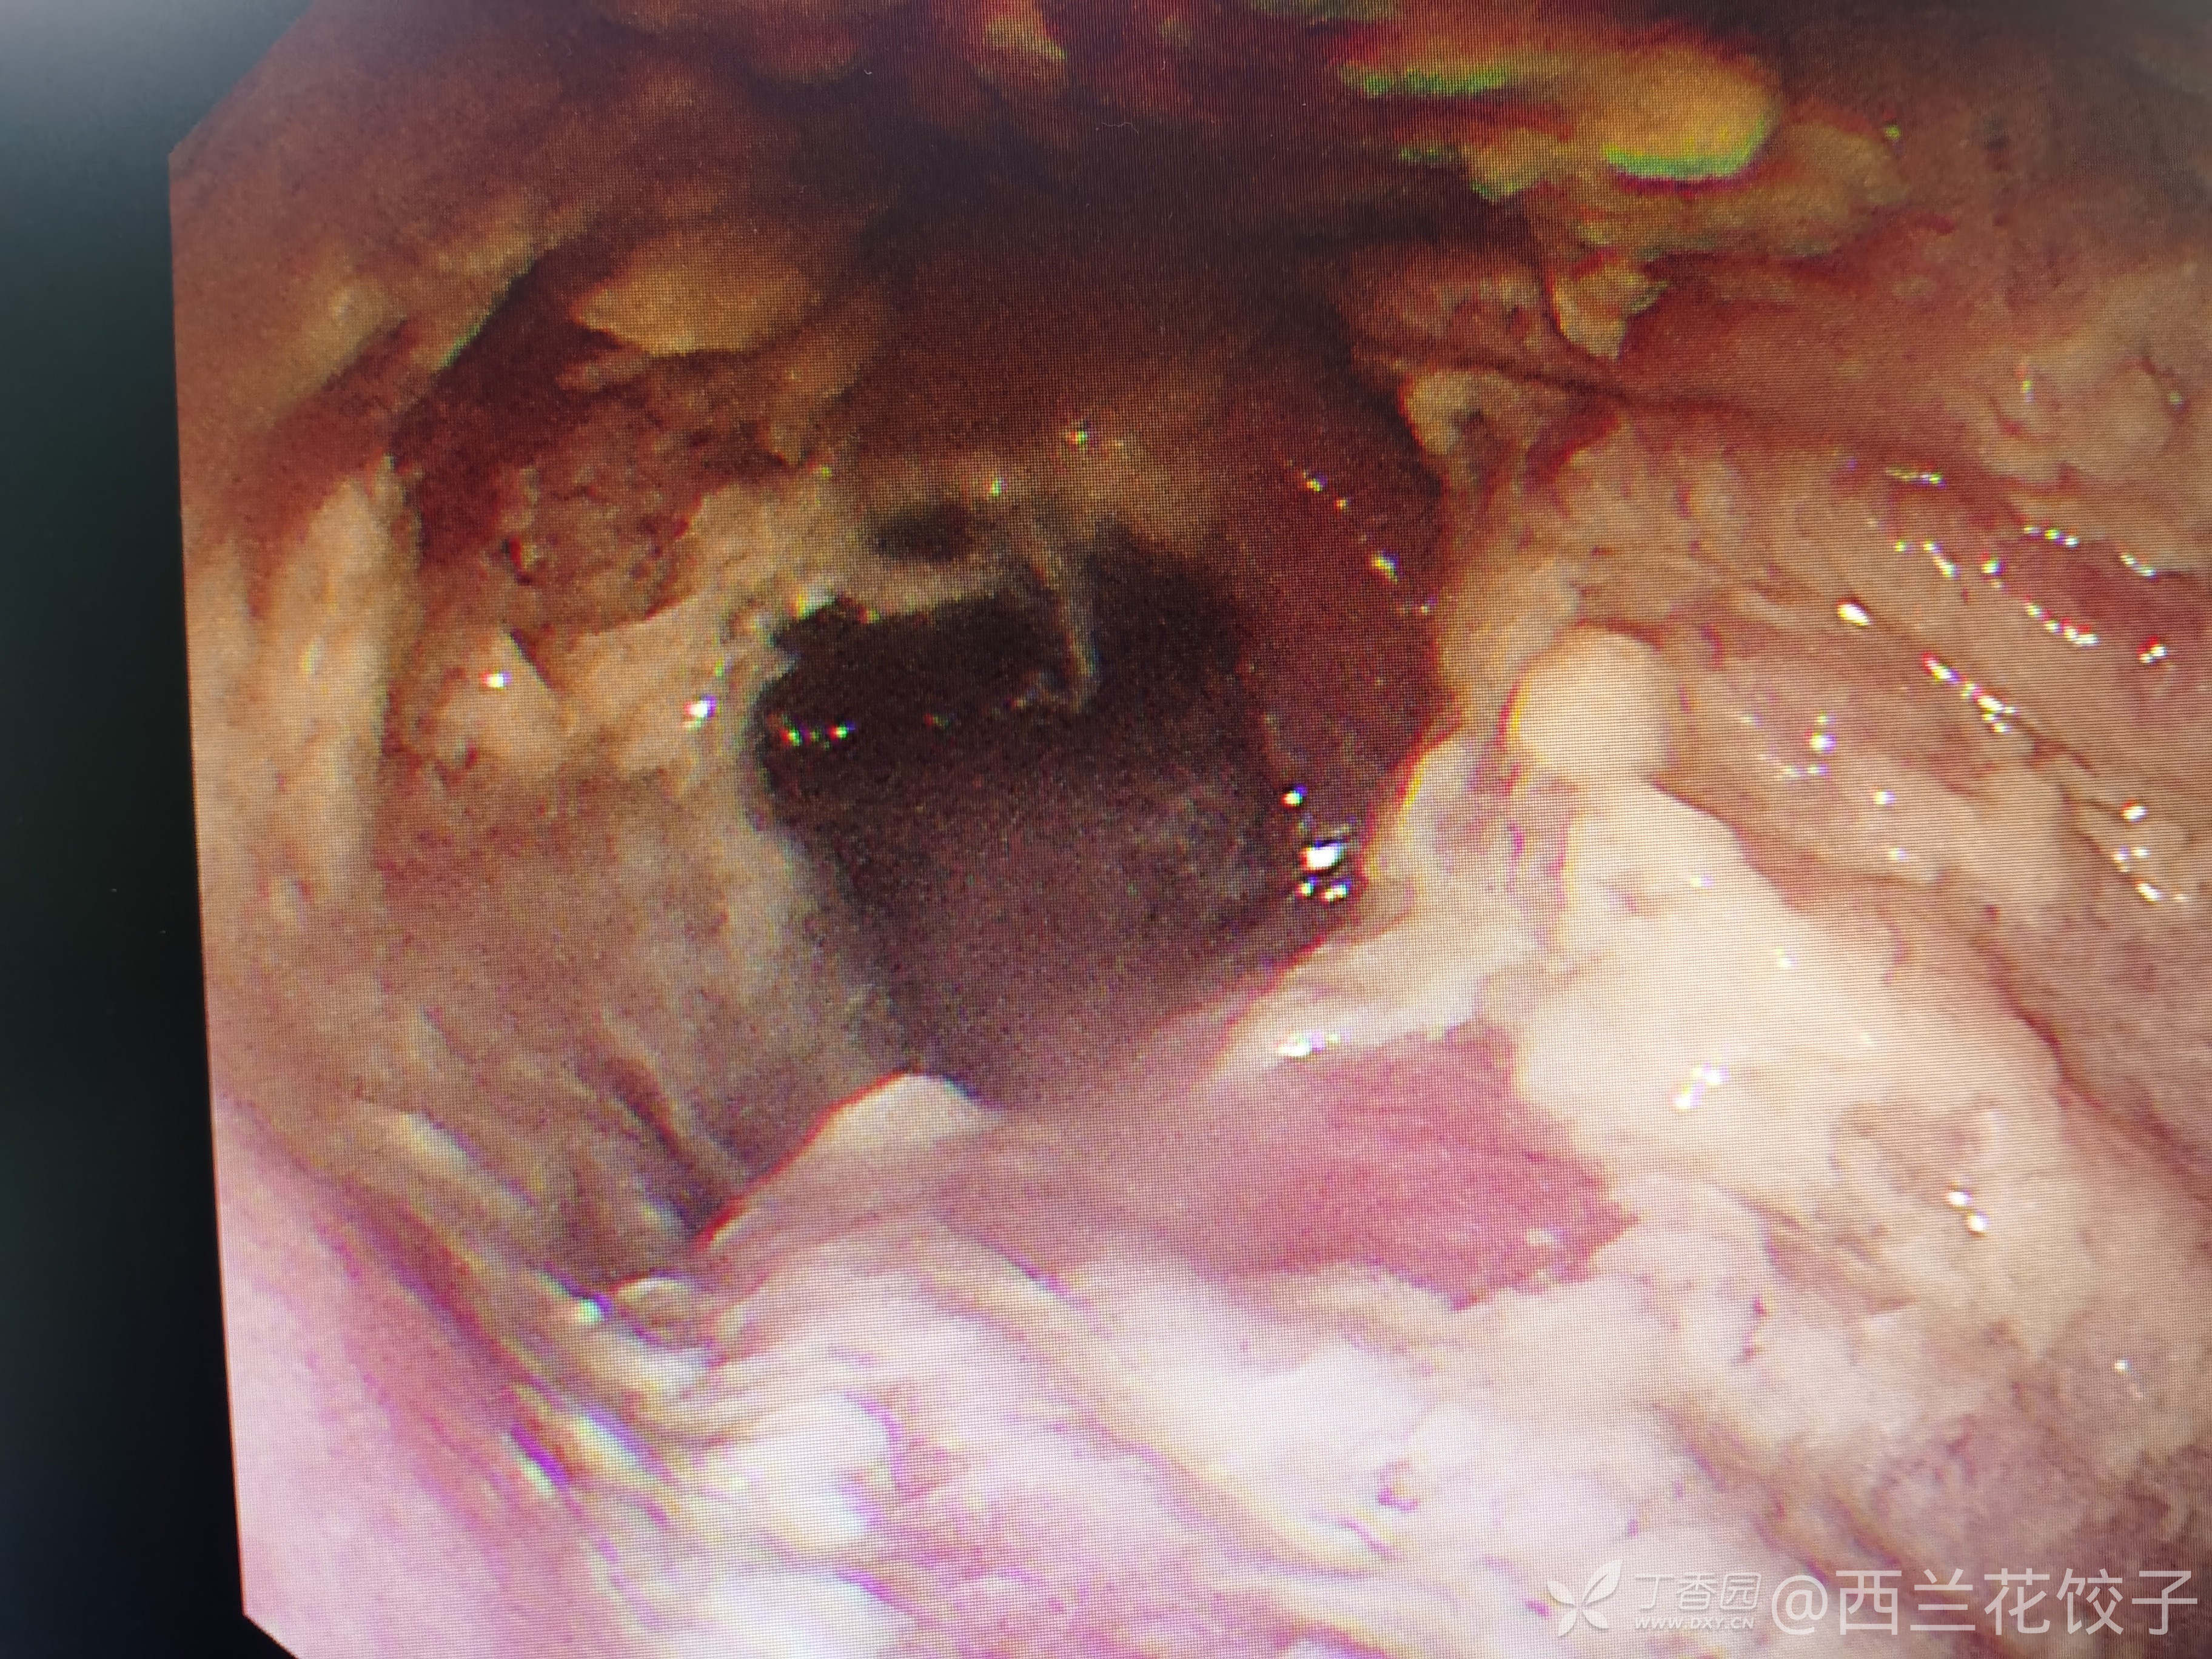

辅助检查:胃镜检查如下,食管内可见大量食物残渣及液体,胃腔内未见明显异常,胸腹部Ct如下,新冠核酸阴性。